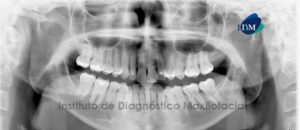

Paciente masculino, 11 años de edad es referido al Instituto de Diagnostico Maxilofacial (IDM) para evaluación general.A la evaluación de la radiografía panorámica (ortopantomografía) se